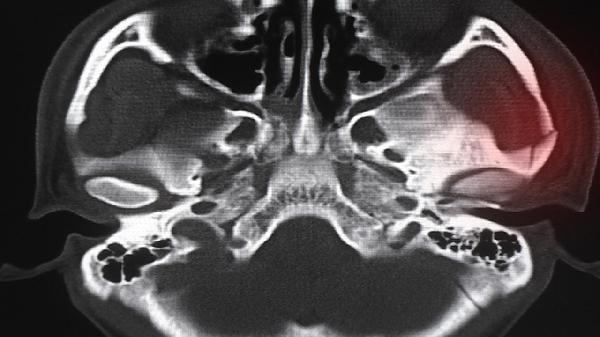

建议选择具备颌面外科资质的医疗机构,术前通过三维CT扫描设计个性化方案。术后配合冰敷、抗感染治疗及流质饮食,定期复查评估恢复情况。非手术替代方案可考虑玻尿酸或脂肪填充,但维持时间较短,适合轻度凹陷改善。